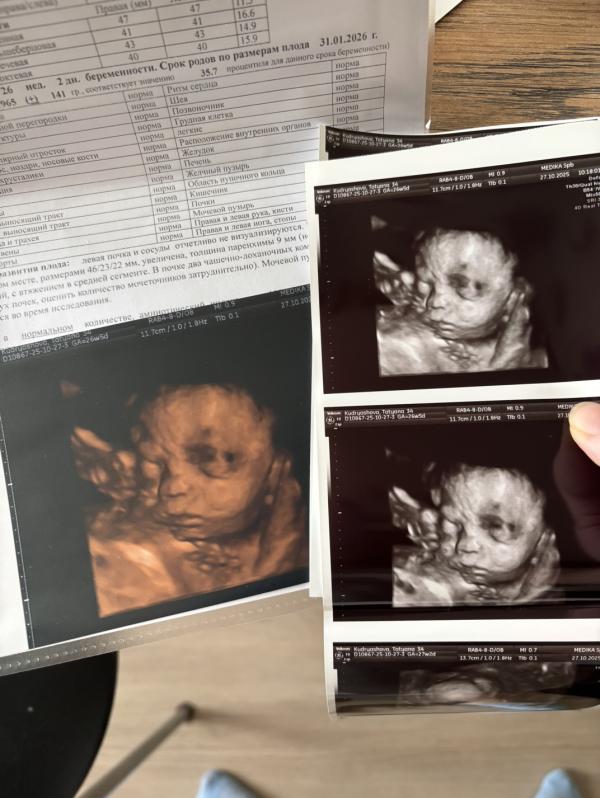

Ну что, была сегодня на встрече с нашим мальчишкой) И знаете что?) Оказалось, что он дочкин близнец) Это удивительно) Будто просто немного припоздал)

По узи подтвердили отсутствие левой почки, правая увеличенная, врач сказала, что это похоже либо на удвоение почки, либо на то, что 2 почки просто слились в одну, тк внутри по узи присутствуют 2 лоханки и будто бы к ней ведут 2 сосуда, будто к 2 почкам. Больше пока до родов ничего сказать нельзя. В остальном ттт все без особенностей🙏🏻 Ждём 3 скрининг через месяц.

Обалдеть! Реально копия! 😻 здоровье крошке! Ттт